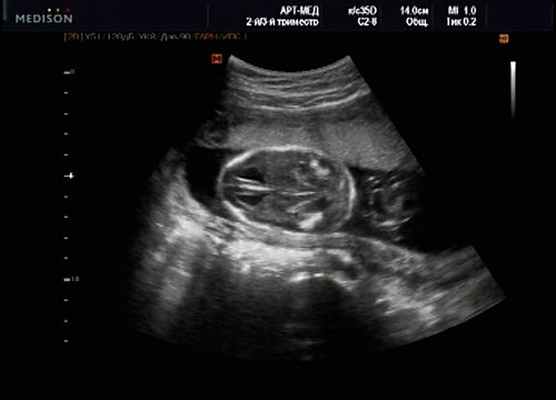

Клиническое наблюдение 2

Беременная М., 21 года. Впервые обратилась в клинику в срок 20 нед беременности. Исследование проводилось на аппарате SonoAce-R7 (Samsung Medison) с использованием режима поверхностной объемной реконструкции 3D/4D. При изучении позвоночника плода в трех плоскостях костных деформаций не выявлено. В грудном отделе позвоночника обнаружено тонкостенное кистозное образование с анэхогенным содержимым, стебельчатой формы (рис. 10-12). Степень "прозрачности" содержимого была выше околоплодных вод, что позволяло идентифицировать его как ликвор. В проекции грыжевого выпячивания располагалась петля пуповины, дифференциальную диагностику которой без труда удалось провести с помощью ЦДК (рис. 13).

У плода наблюдалась выраженная гидроцефалия, обусловленная синдромом Аронольда - Киари II (рис. 14, 15).